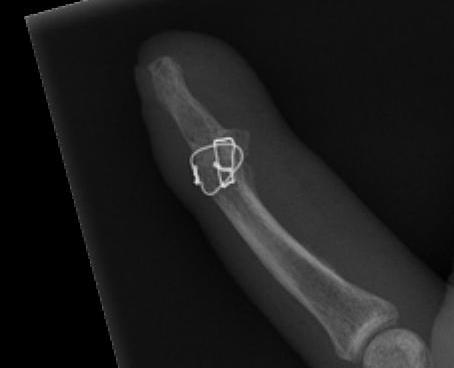

C. Longitudinal K wire and TBW figure 8

- pass wire retrograde

- reduce, pass distally into P2